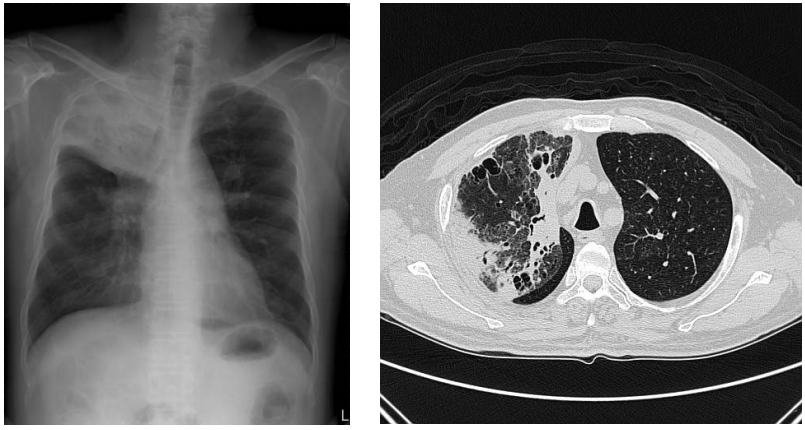

73 56 歲男性抽菸病人,主訴胸痛和咳嗽,胸部影像如附圖,則最可能的診斷為下列何者?

(A)右肋膜積液 (B)右肺擴張不全(Atelectasis) (C)前縱膈腔腫瘤(Anterior mediastinal tumor) (D)右肺上葉肺炎(Lobar pneumonia)